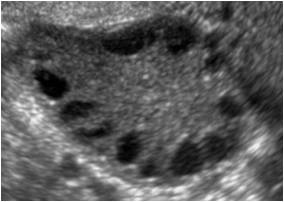

- Aspecto policístico ao ultrassom – Inicialmente através do achado de 12 ou mais folículos (medindo 2-9mm) na periferia do ovário ou ovário com volume maior do que 10cm3. No entanto, como esse achado está presente em muitas mulheres sem sintoma nenhum, já se recomenda que para diagnóstico de ovário com aspecto micropolicístico haja mais do que 25 folículos. Percebam que há critérios bem definidos. Agora busque lá seu ultrassom e veja se esses critérios estão presentes para que o laudo seja “aspecto micropolicístico”. Perceba que ter cistos no ovário não significa necessariamente ter síndrome dos ovários policísticos. Se você só tem a imagem ao ultrassom e não tem outros sintomas você não tem SOP.

Perceba que os cistos devem estar dispostos na periferia do ovário